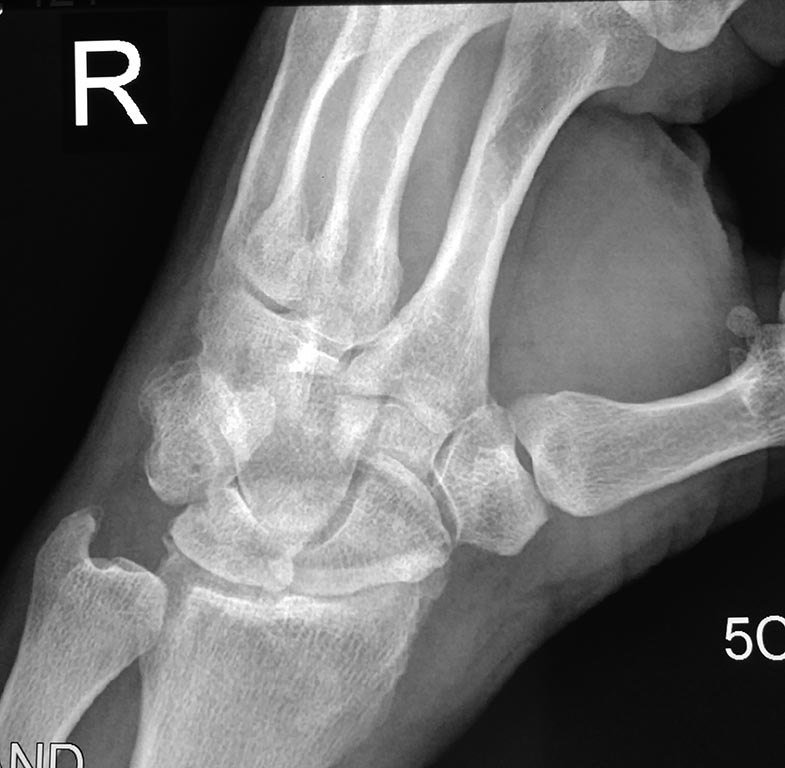

Для начала нужно говорить о тактике обследования. Если не КТ, то хотя бы косую проекцию для вывода ладьевидной кости. И боковую, конечно. Подобные долгоиграющие травмы чаще всего бывают при ложных суставах ладьевидной кости. А здесь уже есть артроз между лучевой и ладьевидной костями. Расширено расстояние между ладьей и полулунной. Скорее всего замешана ладьевидная кость.

Четкая картина SLAC, положительный симптом "кольца", Терри Томаса.

Согласен. Диастема Томпсона, а вот что с ней делать?

Боль преимущественно где в суставе? Похоже перелом боксера был и трехгранной кости. Плюс артроз есть.

"Боксерского" перелома не видно. Какой-то "кусок" кости "болтается", но непонятно, откололся от лучевой или от трехгранной. То есть налицо признаки бывшей травмы, но никак не аутоиммунного процесса.